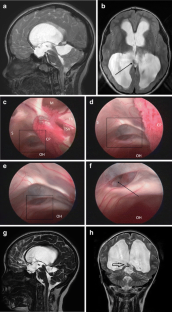

Cinalli G, Cappabianca P, de Falco R, Spennato P, Cianciulli E, Cavallo LM, Esposito F, Ruggiero C, Maggi G, de Divitiis E (2005) Current state and future development of intracranial neuroendoscopic surgery. Expert Rev Med Devices 2:351–373

Cinalli G, Sainte-Rose C, Chumas P, Zerah M, Brunelle F, Lot G, Pierre-Kahn A, Renier D (1999) Failure of third ventriculostomy in the treatment of aqueductal stenosis in children. J Neurosurg 90:448–454

Cinalli G, Sainte-Rose C, Simon I, Lot G, Sgouros S (1999) Sylvian aqueduct syndrome and global rostral midbrain dysfunction associated to shunt malfunction. J Neurosurg 90:227–236

Cinalli G, Salazar C, Mallucci C, Yada JZ, Zerah M, Sainte-Rose C (1998) The role of third ventriculostomy in the management of shunt malfunction. Neurosurgery 43:1323–1329

Cinalli G, Spennato P, Cianciulli E, D’Armiento M (2004) Hydrocephalus and aqueductal stenosis. In: Cinalli C, Maixner WJ, Sainte-Rose C (eds) Pediatric hydrocephalus. Springer, Milan, pp 280–293

Cinalli G, Spennato P, Ruggiero C, Aliberti F, Maggi G (2004) Aqueductal stenosis 9 years after mumps meningo-encephalitis. Treatment by endoscopic third ventriculostomy. Childs Nerv Syst 20:61–64